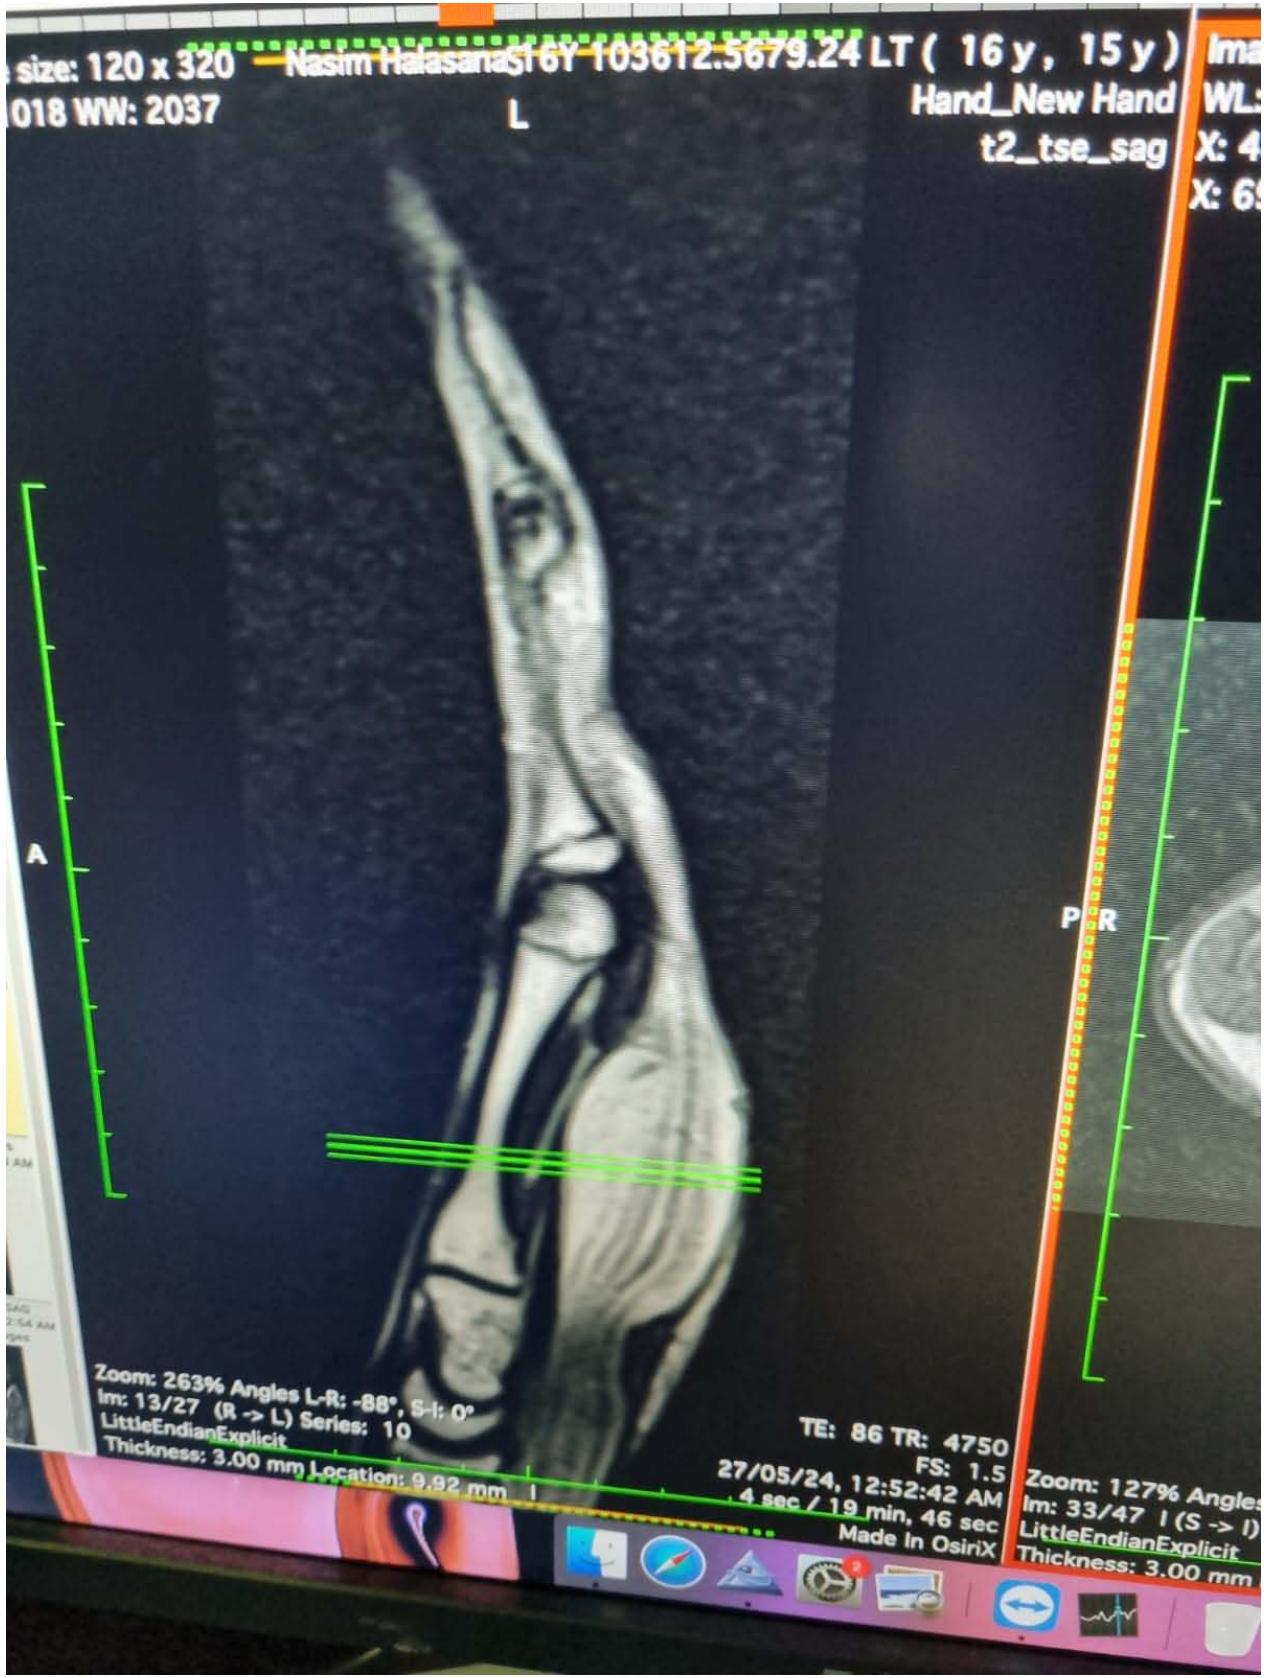

All routine blood investigations with Xray of left hand was done. Plain radiograph showed no bony abnormality. The possible differential diagnoses considered were ganglion cysts, vascular malformations, schwannomas, neurofibromas, and lipomas. An ultrasound of the wrist revealed enlarged and hypoechoic nerve fascicles surrounded by echogenic fat tissue, giving a "cable-like appearance" on axial images. MRI of the left wrist, showed diffuse thickening of nerve fascicles of the median nerve, extending from the distal forearm to the wrist and into the distal palmar region. There was diffuse and extensive interfascicular and perineural lipomatous infiltration, with the nerve fascicles shows mild diffuse enhancement on post-contrast study. The radiological diagnosis was fibro lipomatous hamartoma of the median nerve.

Figure 8: Magnetic Resonance imaging of Lipofibromatous Hamartoma with coaxial cable-like appearance